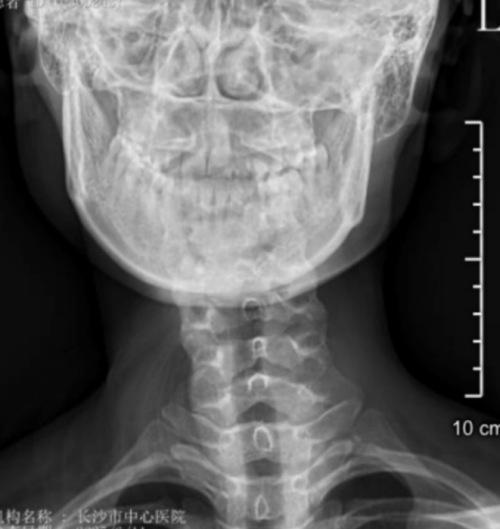

李琳出生后没多久,细心的父母就发现女儿的脖子总是向右倾斜,起初以为是睡姿问题,可随着年岁增长,这个“小毛病”不仅没有消失,反而带来了更多困扰:颈椎逐渐变形、肩背持续疼痛,连最简单的转头动作都变得困难。

“患者属于典型的先天性肌性斜颈,由于延误治疗,颈部肌肉已形成纤维化改变。”该院脊柱外科二区主任、副主任医师曾浩介绍。面对这个特殊病例,医疗团队决定采用先进的微创技术——通过仅3厘米的切口,在放大数倍的手术视野下,精准松解挛缩的胸锁乳突肌,同时保护重要的神经血管。

与传统手术相比,这种微创方式具有显著优势:一是创伤小,切口仅为传统手术的1/3;二是恢复快,术后即可下床活动;三是更美观,采用美容缝合,疤痕几乎不可见。